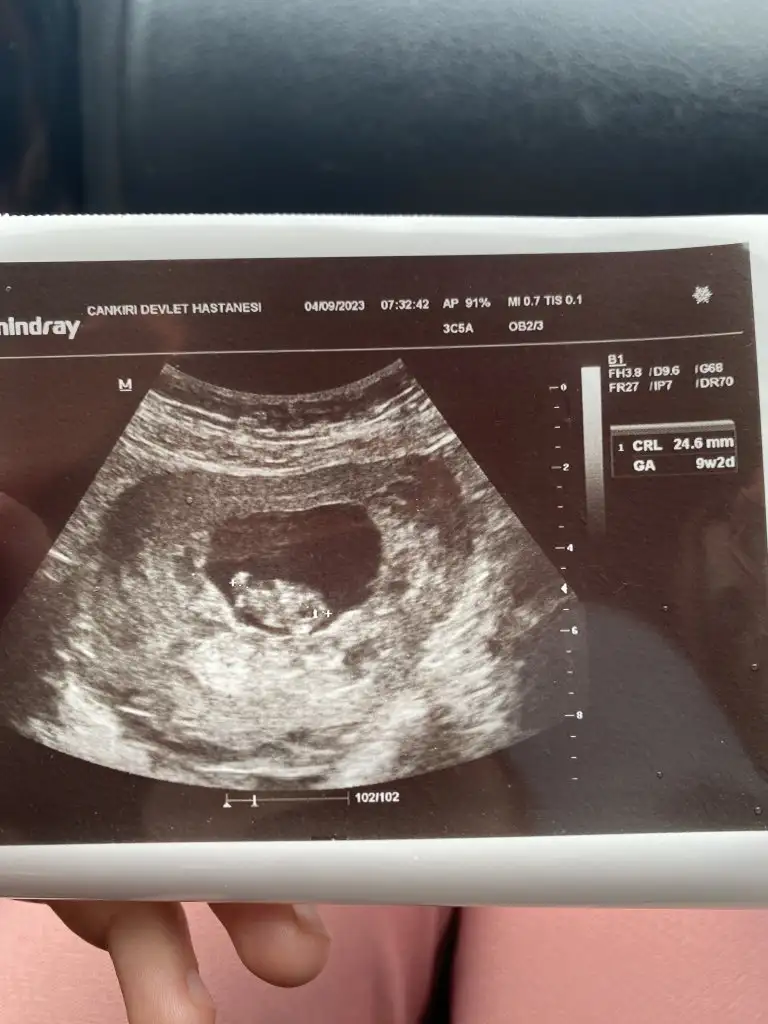

Erkek9 hafta 2 günlük bize de yorum yapar mısınızz

Nub teorisi evet, biraz da kalbim temiziyi de bunu atanlar %100 doğru olmadığını biliyor zaten...meraktan atıyoruz ki sanırım nub teorisine göre bakıyor dalga geçilcek bişi var mı bilemedim